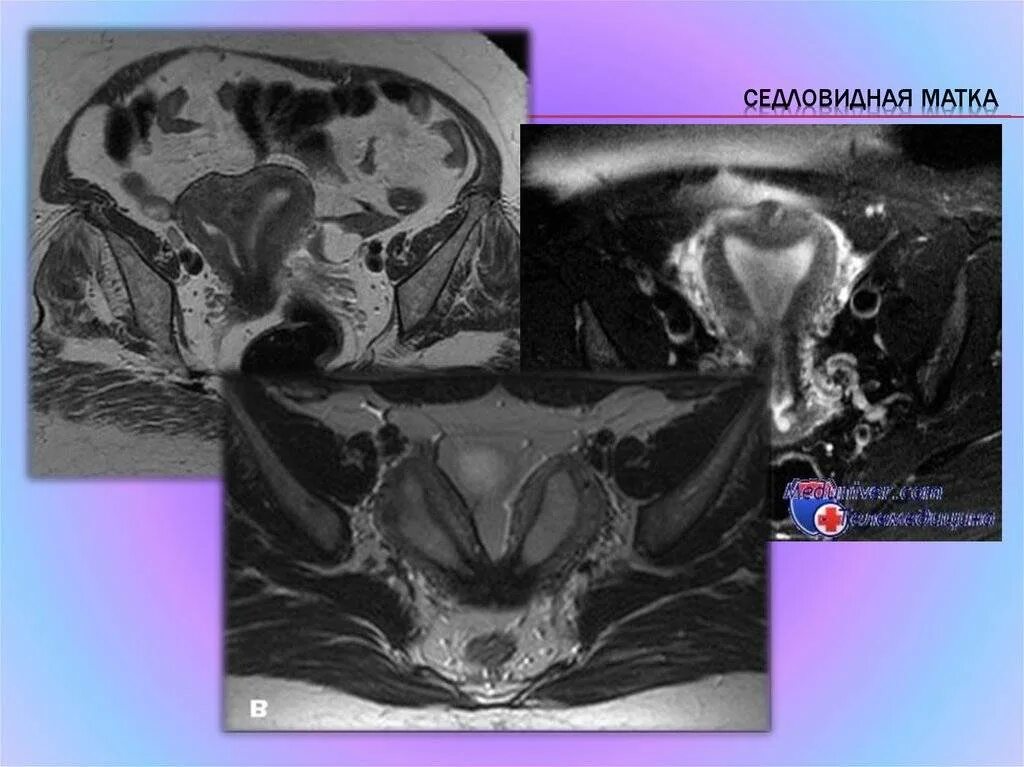

Смешанные матка